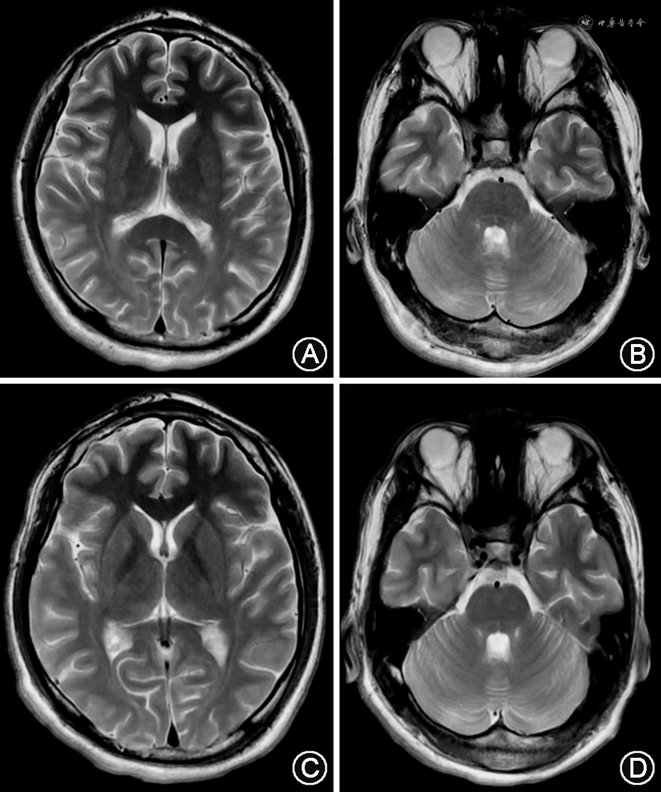

实验室检查:血、尿、粪便常规,肝、肾功能,血脂、血糖以及电解质、甲状腺功能均无明显异常。脑电图:用药前24 h动态脑电图(2020年11月15日,于外院检测故具体图像未提供)示监测期间可见多量低中幅尖波发放,以左侧中央区、顶区、前、中颞区为著;用药后视频脑电图(2022年5月11日)示正常青少年视频脑电监测(图1)。头颅MRI未见明显异常(图2A、B)。外院肌电图(2020年10月15日)示右胫后神经F波未引出;左胫后神经F波潜伏期正常,波幅降低,出现率100%;双正中神经F波潜伏期均正常,波幅均降低,出现率100%。我院肌电图(2022年5月11日)示左正中神经F波潜伏期正常,波幅降低,出现率100%,双胫后神经F波均未引出。交感皮肤反应(sympathetic skin reaction,SSR):刺激左正中神经,于双手、双足记录,双手、双足SSR均未见肯定波形。体感诱发电位(somatosensory evoked potentials,SEP;2022年5月11日):双上肢方波分别刺激左、右正中神经,双侧Erb电位(N9)各波潜伏期及波幅均正常,波形分化及可重复性均可,双侧颈髓电位(N13)潜伏期均延长,波幅均正常,波形分化及可重复性均可,双侧皮质电位(P15、N20、P25)各波潜伏期均延长,波幅明显增高(巨大电位),波形分化及可重复性均可;双下肢方波分别刺激左、右胫后神经,双侧皮质电位(P40、N50、P60)各波潜伏期均延长,波幅明显增高(巨大电位),波形分化及可重复性均可(图3)。视觉诱发电位(visual evoked potentials,VEP;2022年5月11日):闪光刺激左眼,枕记录,左眼VEP P100多次重复刺激均未见肯定波形;闪光刺激右眼,枕记录,右眼VEP P100多次重复刺激均未见肯定波形。脑干听觉诱发电位:双耳正常。眼科检查见双眼眼底黄斑区存在樱桃红斑(图4);光学相干断层成像示黄斑形态正常。

实验室检查:血、尿、粪便常规,肝、肾功能,血脂、血糖以及电解质、甲状腺功能均无明显异常。2021年2月1日动态脑电图示中度异常脑电图,醒睡各期双侧额、中央、顶、中颞区棘慢波发放;2022年5月11日用药后视频脑电图示异常青少年视频脑电监测;睡眠期中央、Cz区多量棘慢复合波散发(图5)。头颅MRI未见明显异常(图2C、D)。肌电图(2022年5月11日):左正中神经F波潜伏期正常,波幅降低,出现率100%;左胫后神经F波潜伏期正常上限,波幅降低,出现率70%;右胫后神经F波未引出。SSR:刺激左正中神经,于双手、双足记录,双手SSR多次重复刺激均未见肯定波形,双足SSR潜伏期均正常,波幅均降低,波形分化及可重复性均可。SEP(2022年5月11日):双上肢方波分别刺激左、右正中神经,双侧Erb电位(N9)各波潜伏期及波幅均正常,波形分化及可重复性均可,双侧颈髓电位(N13)潜伏期均延长,波幅均正常,波形分化及可重复性均可,双侧皮质电位(P15、N20、P25)各波潜伏期均延长,波幅明显增高(巨大电位),波形分化及可重复性均可;双下肢方波分别刺激左、右胫后神经,双侧皮质电位(P40、N50、P60)各波潜伏期均延长,波幅明显增高(巨大电位),波形分化及可重复性均可(图6)。VEP(2022年5月11日):闪光刺激左眼,枕记录,左眼VEP P100未见肯定波形;闪光刺激右眼,枕记录,右眼VEP P100未见肯定波形。脑干听觉诱发电位:双耳正常。眼科检查见双眼眼底黄斑区存在樱桃红斑(图7);光学相干断层成像:黄斑形态大致正常,中心凹神经上皮质反射增强,右眼较明显。

从临床表现看,ST-1起病晚、病情较轻,常无明显的身体畸形。本文中2例患者最显著的症状为进行性加重的肌阵挛发作,通常发生于情绪激动时或劳累后,伴意向性震颤、精细运动困难、行走不稳的表现,同时伴发作性意识丧失,与该疾病特征性肌阵挛、小脑性共济失调、癫痫发作相一致。视力减退常进行性加重,并伴双侧黄斑樱桃红色斑点,随着病情进展,该斑点可能会逐渐消失[7]。2例患者日常生活均未配戴矫正眼镜,但入院后完善相关检查,双眼矫正视力均较差且VEP提示双眼传导通路异常,这表明二人均已出现明显的视力减退表现;眼底检查提示双侧黄斑区存在樱桃红斑,符合ST-1特征性表现。不同于ST-2,ST-1患者的认知功能正常,可与其他进行性肌阵挛癫痫伴认知功能障碍疾病相区别[8]。本文中2例患者的远、近记忆力,计算力均未见明显减退,可支持此诊断。MRI的异常也很少见,大脑皮质萎缩或小脑萎缩是ST-1患者头颅MRI最常见的异常表现,可出现于疾病的各个阶段[9, 10]。在少数报道中,患者可出现严重小脑萎缩、额颞脑软化或小脑脊膜膨出表现[11, 12]。文中2例患者均存在指鼻、跟膝胫试验不稳及行走摇晃表现,具备共济失调特征,但2例患者头颅MRI检查均未见明显异常,考虑与运动引起的肌阵挛相关。唾液酸沉积症患者SEP中常见巨大诱发电位,提示患者的感觉皮质存在高兴奋性,但此表现不具特异性,且有研究结果显示巨大电位在药物治疗前后无明显改变[13],这与文中2例四肢诱发电位均出现皮质电位各波潜伏期均延长、波幅明显增高(巨大电位)相符合。2例患者F波及SSR的异常,提示患者存在周围神经损害的表现。Steinman等[14]曾报道了1例电生理提示感觉运动性多发性神经病的ST-1患者,之后尚未有相关ST-1患者外周神经受累的描述。需要进一步研究、整合,以确定这一问题的特点。ST-1患者的异常脑电图常呈弥漫性阵发性表现[15],例1在发病期间的脑电图检测结果提示多量低中幅尖波发放,以左侧中央区、顶区、前、中颞区为著;例2存在睡眠期中央、Cz区多量棘慢复合波散发。2例的脑电图结果均提示发作性肢体抽动为癫痫性肌阵挛发作。例1在应用抗癫痫发作药物后,再次监测24 h动态脑电图提示恢复正常;例2用药后的脑电图仍提示异常,这可能与其前期未服用奥卡西平有关。奥卡西平可通过阻断电压依赖性钠通道,稳定过度兴奋的神经元细胞膜,以起到抑制神经元的重复放电,减少突触冲动的传播的作用[16]。这表明2例患者脑电图表现的不同,可能与其前期所服用药物种类、数量不同相关。